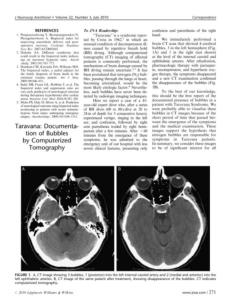

The authors report a case of a 41-year-old expert diver

who, after a series of brath hold dives (60 to 80s/dive at

20 to 24m of depth for 5 consecutive hours), experienced

vertigo, ringing in the left ear, and confusion, followed by

right arm paresthesia trailed by right hemi-paresis after a

few minutes. After <60 minutes from the emergence of

these symptoms, he was admitted to the emergency unit

of our hospital with less severe clinical features, presenting

only confusion and paresthesia of the right hand.